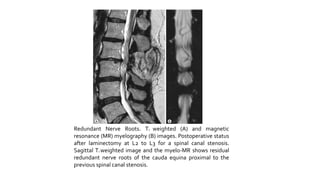

Redundant Nerve Roots. T2 weighted (A) and magnetic

resonance (MR) myelography (B) images. Postoperative status

after laminectomy at L2 to L3 for a spinal canal stenosis.

Sagittal T2 weighted image and the myelo-MR shows residual

redundant nerve roots of the cauda equina proximal to the

previous spinal canal stenosis.